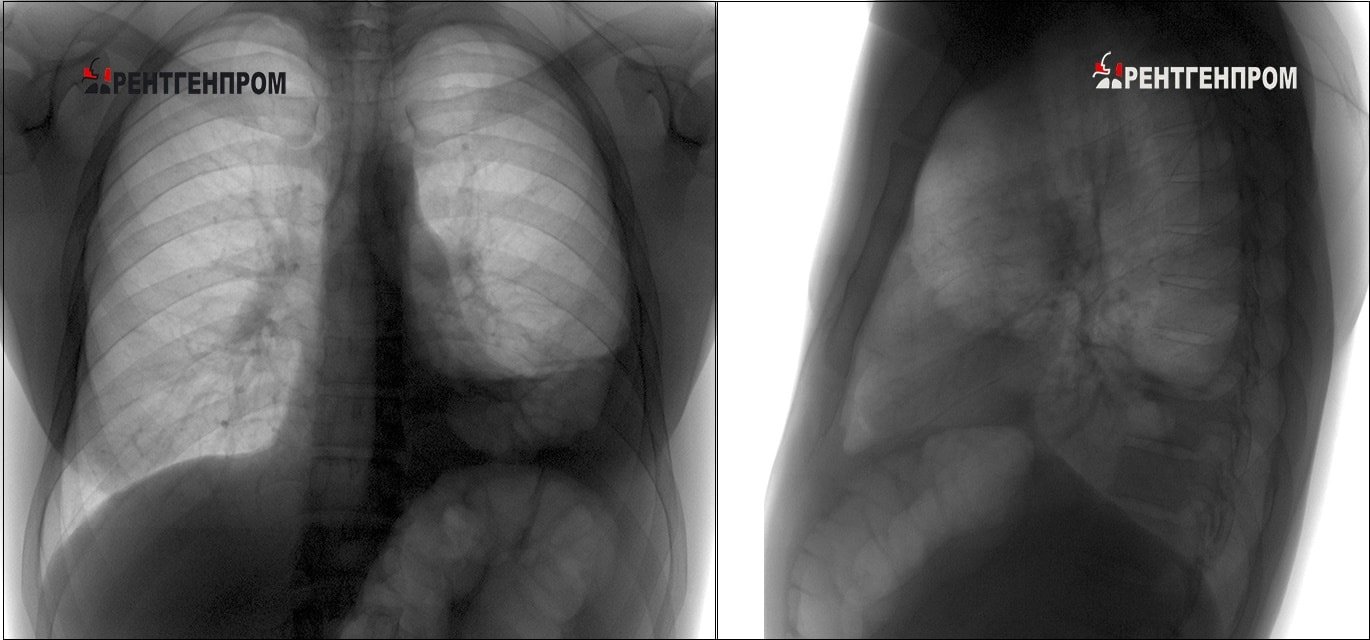

Разница между флюорографией и рентгеном

Существенной разницы между флюорографическим исследованием и рентгеном нет, поскольку изображение при обеих видах исследования получается путём прохождения лучей сквозь тело человека.

image Рентген. (В двух проекциях)

Различия состоят в том, что рентген имеет большую степень излучения и информативность, нежели флюорография. Не рекомендовано делать флюорографию без показания чаще одного раза в год. Исключение составляют отдельные категории населения, которые работают в больницах, школах, призываются на воинскую службу. Рентгеновское исследование большую дозировку, поэтому назначается исключительно по показаниям, например, если результаты флюорографии вызывают подозрение на туберкулёз.